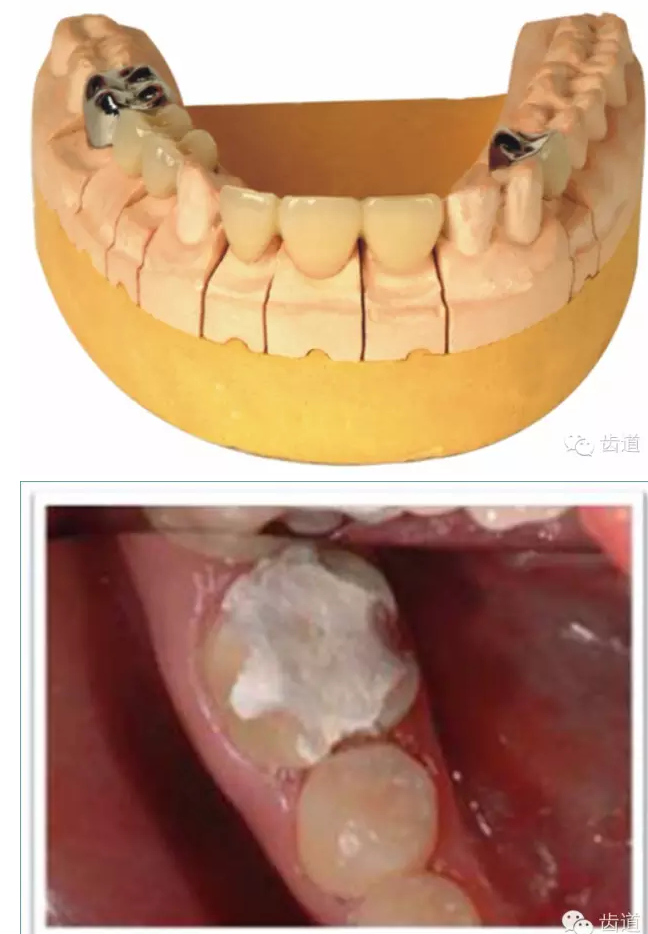

l基牙具有良好的固位形

l基牙具有良好的抗力形

正壓力:即修復體的密貼程度(小于0.2mm)

表面粗糙程度

牙的外形及洞形的幾何形狀:主要是牙體制備出一定聚合角度產(chǎn)生的阻擋作用